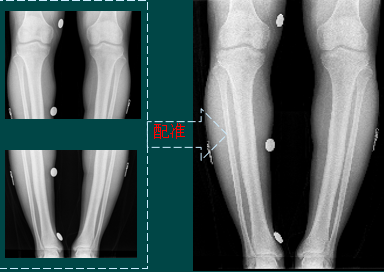

四肢

图像拼接

图像拼接(背景)

图像拼接是将数张有重叠部分的图像(可能是不同时间、不同视角或者不同传感器获得的)拼成一幅大型的无缝高分辨路图像的技术。

图像拼接(结果)